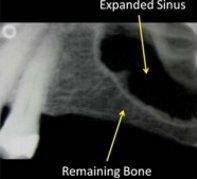

The above X-rays show the expanded sinus before and after bone grafting

The maxillary sinuses are located behind your cheeks and on top of the upper teeth. Sinuses are like empty rooms that have nothing in them. The roots of the natural upper teeth are anchored in the jawbone directly below the sinuses and many of these roots actually extend up into the maxillary sinuses. When upper teeth are removed, the sinuses begin to expand into the extraction regions due to the loss of bony stimulation. This eventually leaves a shallow wall of bone separating the maxillary sinus and the mouth. Dental implants, like your natural teeth, need significant amounts of vertical bony support to hold them in place and in the past, the options available to dentists who replaced missing upper posterior teeth, were limited to removable partial dentures.